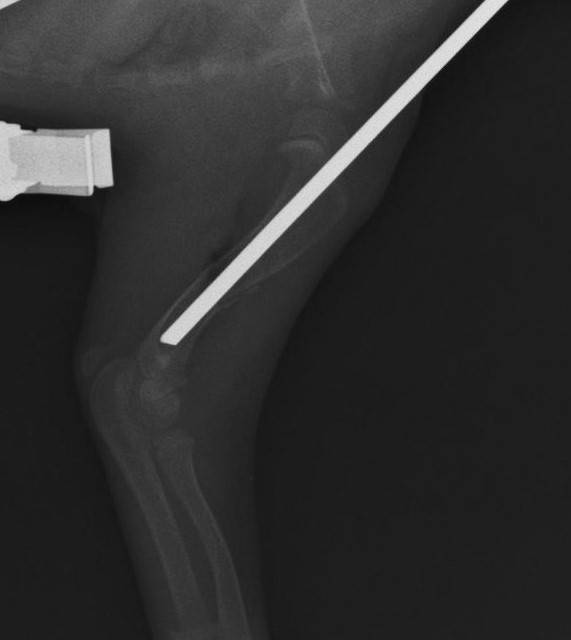

すぐに手術をして、骨折部にピンを挿入し、固定しました。こんな感じです。

もちろんこれだけではちゃんとした固定にならないので、テーピングも行います。

少なくとも2週間くらいはこのまま固定していないと骨折は治りません。